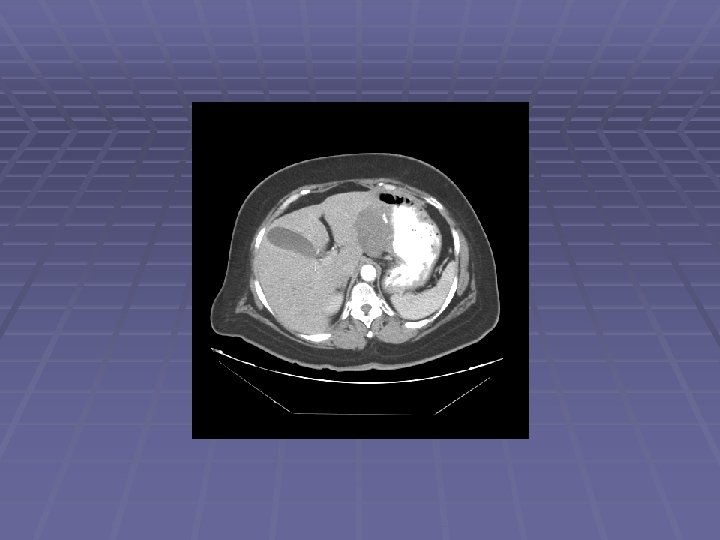

Liver Mass

FNA of Liver Mass

EUS Evaluation of Left Lobe of Liver